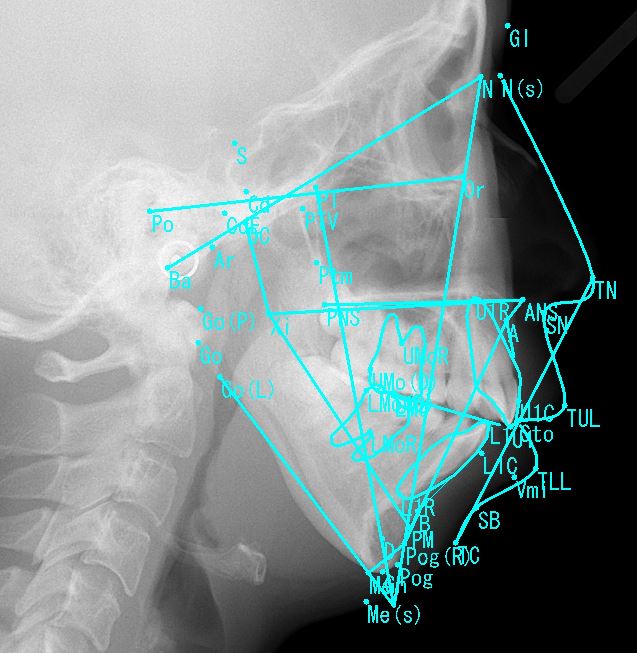

2.レントゲン(パノラマX線写真、側貌セファロ写真、正貌セファロ写真)

👆このセファログラム(頭部X線規格写真)の分析・計測が、矯正歯科の診断では必須であり、重要です!!最近ではCTスキャンを応用する場合もあります。

計測は専門の計測ポイントを利用して、トレースを行い角度や長さを分析します。

計測は専門の計測ポイントを利用して、トレースを行い角度や長さを計測し、分析します。分析方法は色々な方法があり、これは、担当医によって違います(流派のようなものがあります)が、基本的項目は共通しているかと思います。

このレントゲン分析が矯正歯科の診断には必須です。にはこんな感じで行います。